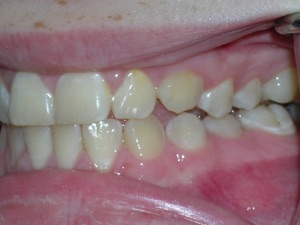

Here’s a fascinating case of a young lady who had a completely blocked out premolar.

With a combination of braces, expansion and trimming we were able to bring it in. Watch!

Here are the results.